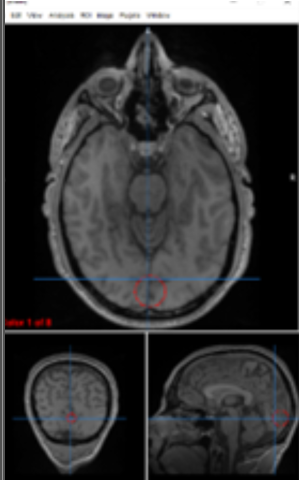

substantia nigra

motor control, reward seeking, learning, emotion

VTA (ventral tegmental area)

dopamine production/rewards/ motivation

optic chiasm

separates visual input

amygdala

primary center for emotional processing, fear conditioning, and threat detection